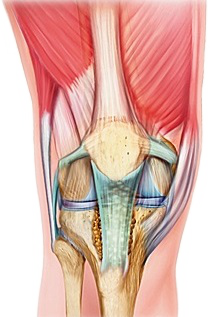

Les ménisques sont des fibro-cartilages interposés de chaque côté des compartiments interne et externe du genou. En forme de croissant ou de quartier de pomme, ils sont solidement attachés en périphérie à l'enveloppe capsulaire et à leurs extrémités antérieure et postérieure au centre du tibia (Figure 1).

En coupe transversale, les ménisques ont une forme triangulaire avec une pér iphérie plus large et bien vascularisée (zone rouge) et un bord libre plus mince et non vascularisé (zone blanche).

De consistance élastique, ils jouent un rôle d'amortissement des contraintes mécaniques et protègent ainsi le cartilage de l'usure ou arthrose. De par leur forme de cale, ils participent avec les ligaments croisés et périphériques à la stabilité du genou.

Figure 1 : anatomie des ménisques (à gauche) et vascularisation périphérique sur une coupe transversale (à droite)